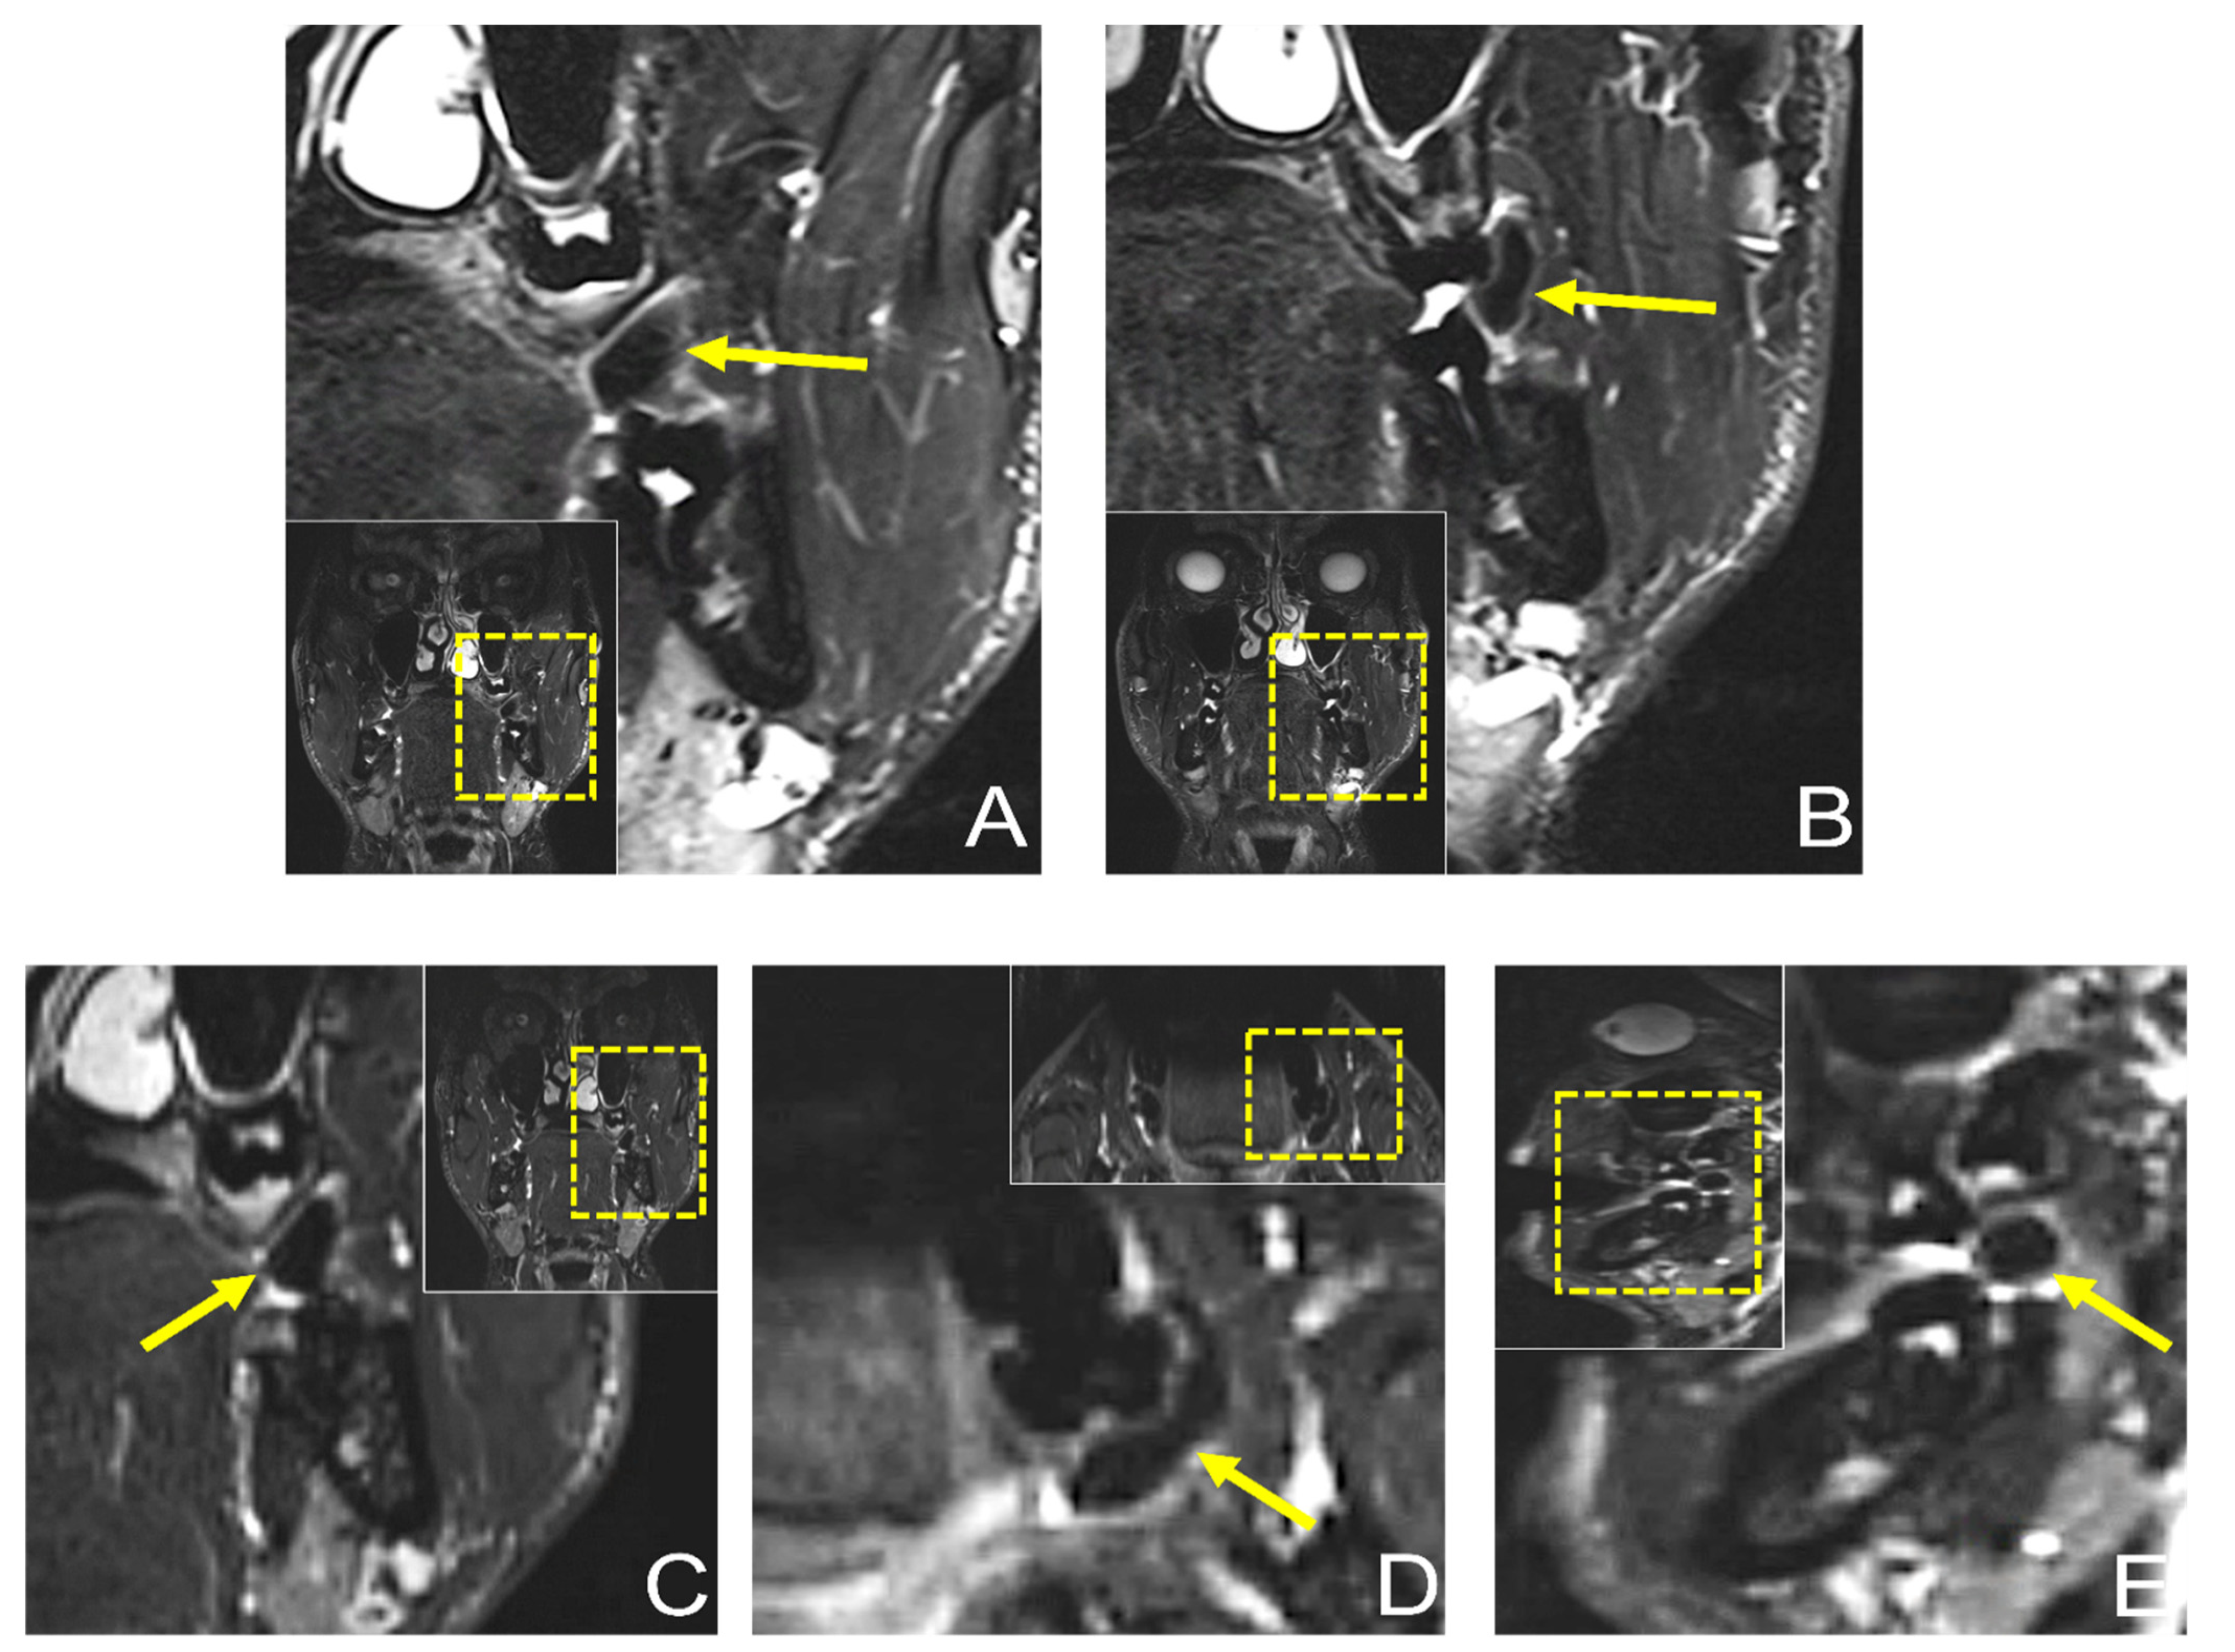

Dental MRI showed a well-demarcated lesion with a maximum extension of 21.3 × 5.6 mm (axial), 13 × 8.6 mm (coronal), and 10.1 × 9.8 mm (sagittal) on a T2 STIR protocol, with homogenous low signal intensity in the central area of the lesion, while the peripheral area showed a high signal intensity. The lesion originated from the planum buccale and did not infiltrate adjacent structures, with a displacement of the second upper molar (Figure 4). The DESS protocol revealed the same hypointense lesion with lower resolution and image quality compared with the STIR protocol (Figure 5). Thus, the radiological findings excluded any further involvement in the head and neck area, the presence of a lipoma, or other space-occupying pathologies, and provided the precise localization and extension of the suspected fibromatous lesion.

Figure 4.

Preoperative dental MRI showed a well-demarcated lesion with a maximum extension of (D) 21.3 × 5.6 mm (axial), (A–C) 13 × 8.6 mm (coronal), and (E) 10.1 × 9.8 mm (sagittal) on a T2 (short-tau inversion recovery) STIR protocol, with homogenous low signal intensity in the central area of the lesion, while the peripheral area showed a high signal intensity. The lesion originated from the planum buccale and did not infiltrate adjacent structures, with (E) a displacement of the second upper molar. For orientation, the dotted rectangles in the corner show the enlarged area.